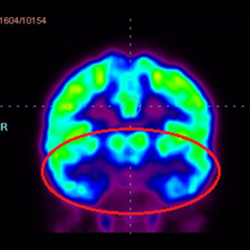

干細胞治療腦癱后改善的客觀放射學證據

細胞治療后,藍色和黑色區域減少,并且看到更活躍的區域。這表明損傷減少并改善了大腦功能。

細胞治療前 PET CT 掃描顯示神經組織中的藍/黑色區域,表明腦癱引起的大腦損傷。

這證明細胞療法是治療腦癱兒童安全有效的方法。細胞療法可以更新大腦損傷的核心,并且可以通過 PET CT 掃描來監測大腦的改善情況。這些細胞療法與標準治療一起促進腦癱兒童的生長和改善。